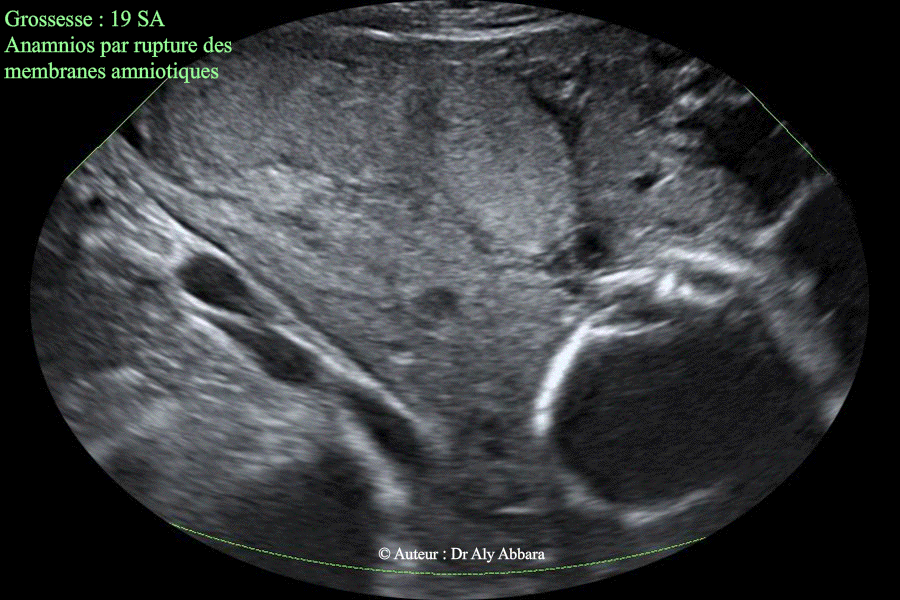

Anamnios par rupture prématurée des membranes à 19 SA - Aspect du placenta

Images échographiques montrant un anamnios à 19 SA ; conséquence d'une rupture prématurée des membranes survenant 36 heures auparavant.

L'image échographique montre l'absence totale de liquide amniotique et avec le repli du placenta sous le fait de la constriction de l'utérus.